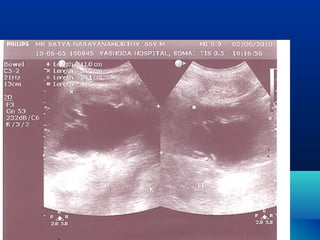

OUR EXPERIENCEOUR EXPERIENCE

โ€ข 96 CASES IN LAST 5 YEARS

โ€ข 18 REQUIRED SURGICAL

INTERVENTION

โ€ข 6 โ€“ PHYSIOLOGICAL

โ€ข 9 โ€“ CALCULUS 6 โ€“ LOWER URETER

3 - UPPER URETER / PUJ

3 โ€“ PUJ OBSTRUCTION - BILAT.